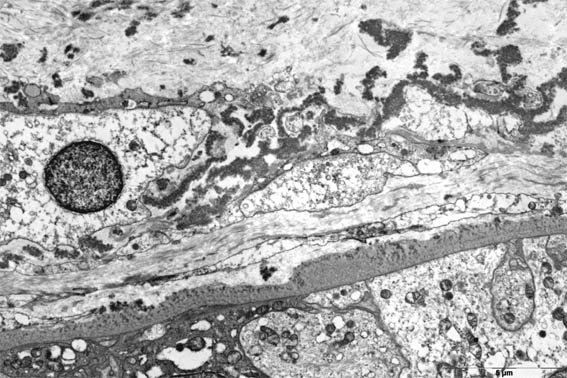

Figura 13.

Microscopía

electrónica, X3.000.